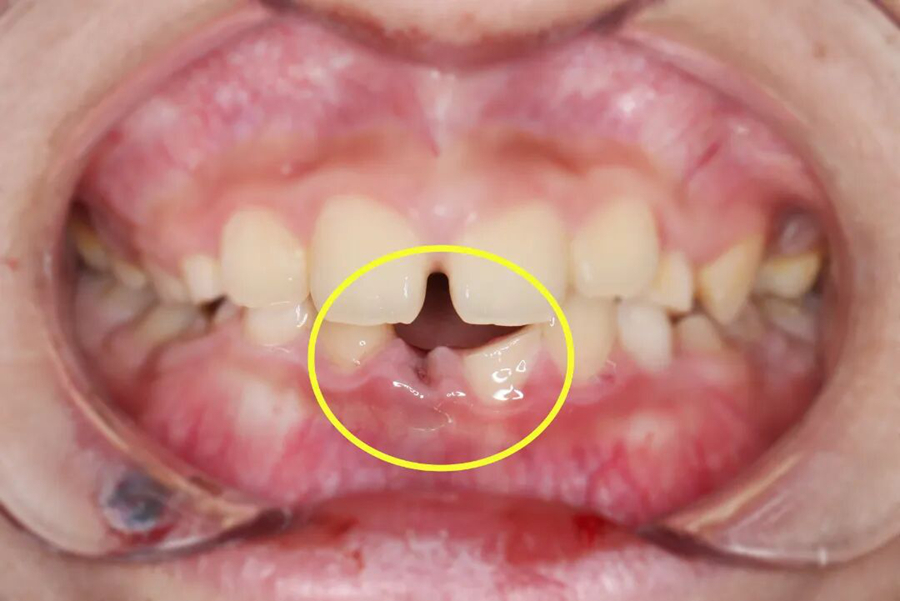

“牙齒脫落時間越久,再植成功率越低,每一分鐘都很關鍵!”口腔中心接診后,立刻啟動急救模式??趦?nèi)檢查和拍片檢查發(fā)現(xiàn),小千脫落的牙齒牙根完整,折斷的牙齒已露髓(可見紅點出血)。

第二步,冠折露髓牙齒修復

針對冠折露髓的牙齒,救治團隊在無痛輔助和顯微鏡下,徹底清除根管內(nèi)的感染組織,進行嚴密的三維根管填充,建立無菌的內(nèi)部環(huán)境。緊接著采用仿生樹脂材料,通過分層分色堆塑技術,精準復原牙齒的天然形態(tài)和色澤,既解決了感染隱患,又恢復了牙齒的美觀和咬合功能。